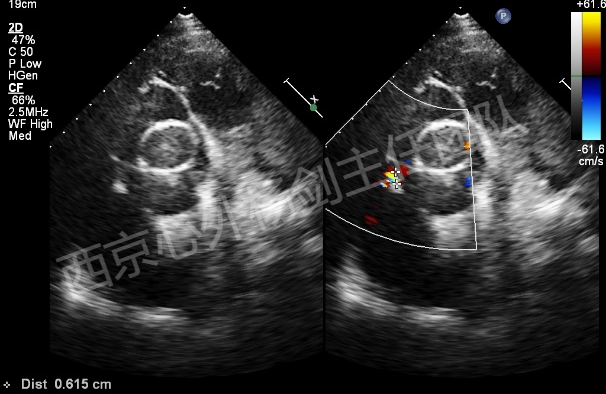

患者李某某,男,61岁,现病史:高血压15年,15年前行主动脉瓣置换术,13年前行升主动脉置换术、冠状动脉旁路移植术。主因心脏瓣膜术后15年,突发胸闷气短20天入院。检查提示:主动脉夹层动脉瘤,主动脉瓣位机械瓣位置、动度未见异常,升主动脉位人工血管上段吻合口漏,原有升主动脉管壁与人工血管之间液区,向右房分流,肺动脉高压(收缩压约51mmHg)。EDV: 192ml, ESV:102ml, FS:23%, SV:89ml。

术中操作